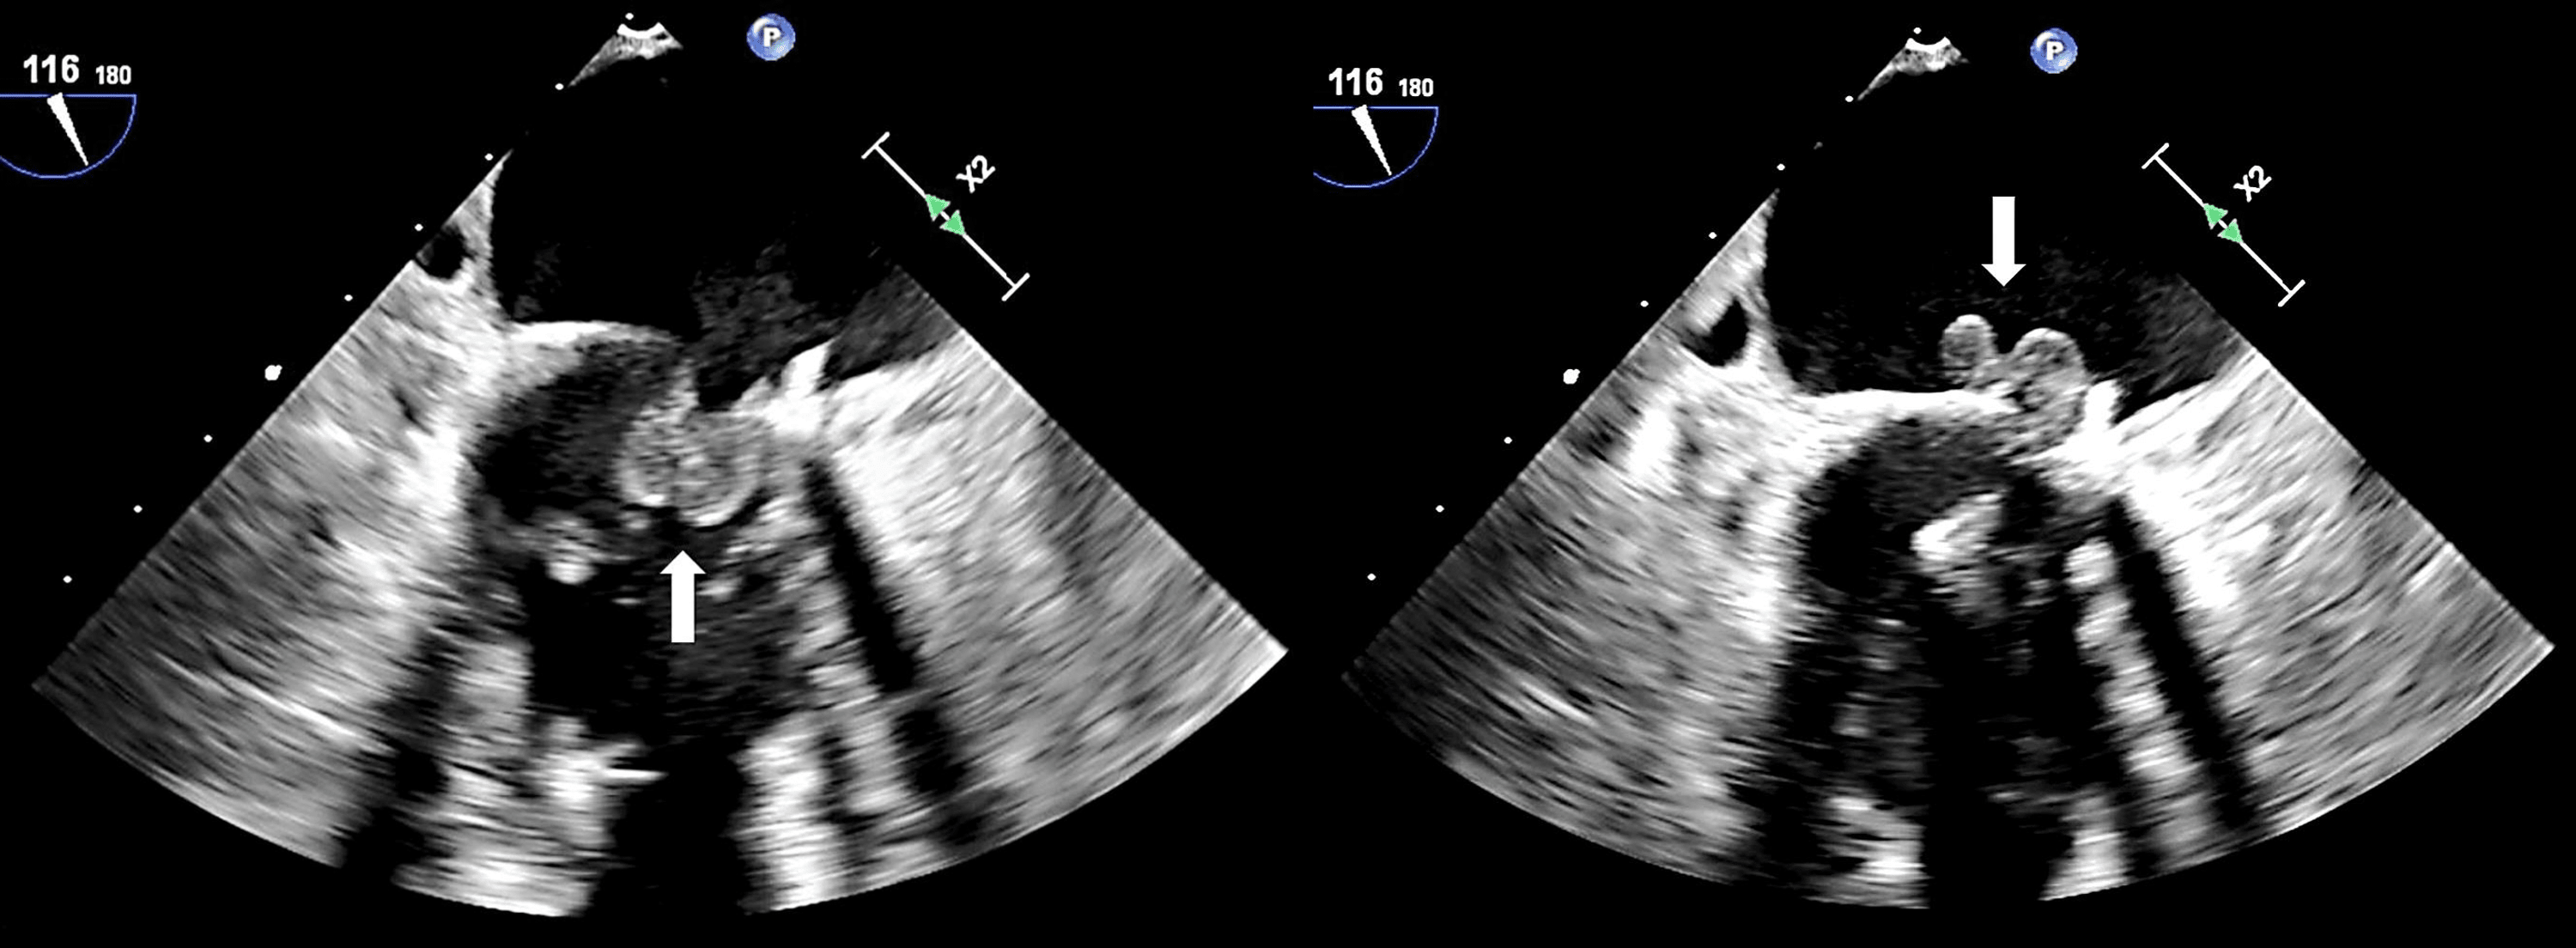

Echocardiogram Aortic dissection with severe aortic regurgitation Movement Artifact At Diastole This study demonstrates the role of careful examination of the physiology of coronary motion in understanding the optimal timing of. Often this technique is conveyed to. While waiting for this magnetisation nulling, due to. Misregistration artifacts, which appear as. The precorrection image (a) shows an artifact in the lad (arrow) due to the acquisition band falling in late diastole/early. Coronary. Movement Artifact At Diastole.

An Unusual Etiology of Aortic Insufficiency A Case Report Cureus Movement Artifact At Diastole Often this technique is conveyed to. Cardiac gating or ecg gated angiography in ct is an acquisition technique that triggers a scan during a specific portion of the cardiac cycle. Coronary ct angiography is a novel noninvasive imaging technology that provides a unique view of cardiac and coronary artery pathologies. However, motion artifact can impair delineation of the coronary artery. Movement Artifact At Diastole.